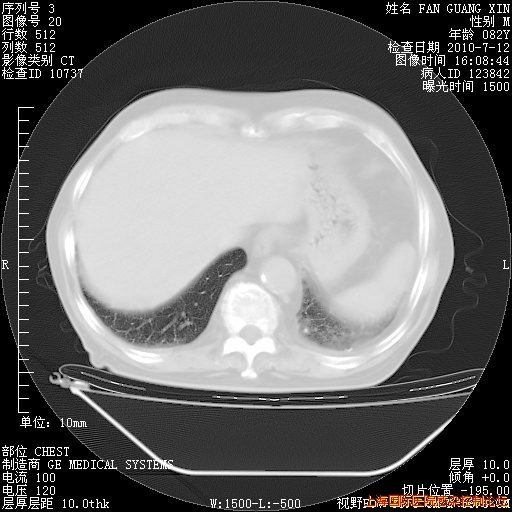

今天复查CT

今天CT

整整相隔30天的肺部CT好像有所好转啊。甲强龙减量第3天,需要观察体温。